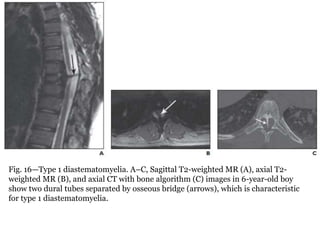

Fig. 16—Type 1 diastematomyelia. A–C, Sagittal T2-weighted MR (A), axial T2-

weighted MR (B), and axial CT with bone algorithm (C) images in 6-year-old boy

show two dural tubes separated by osseous bridge (arrows), which is characteristic

for type 1 diastematomyelia.